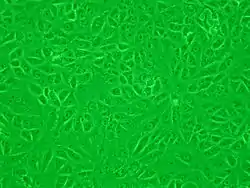

Célula vero

Las células Vero (del esperanto: "verda reno" y "vero" que significan "riñón verde" y "verdad", respectivamente) pertenecen a un linaje celular utilizado en cultivos celulares[1] El linaje Vero fue aislado a partir de las células epiteliales del riñón de un mono verde africano (Chlorocebus sp.; anteriormente llamado Cercopithecus aethiops). El linaje de las células Vero es continuo y aneuploidico, es decir que puede replicarse a través de muchos ciclos de replicación sin envejecer[2] y presenta un número anormal de cromosomas. Permite la producción de vacunas contra enfermedades virales. También se utiliza en estudios científicos de microbiología, biología celular y molecular.